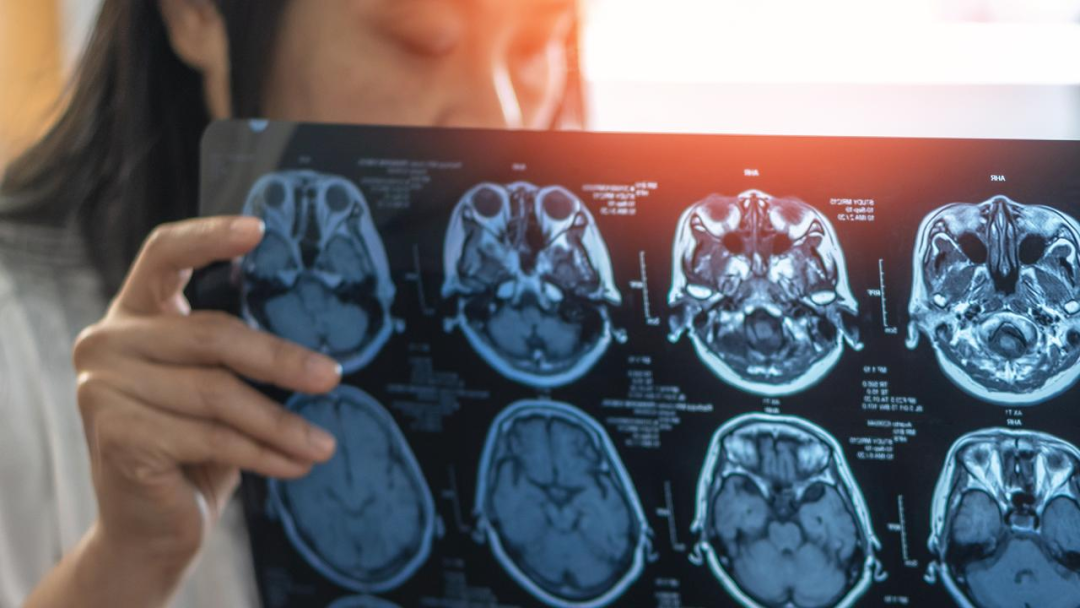

图片来源:news.com.au

痴呆并不是一种特定的疾病。它是一个总称,用于描述许多疾病,特征是影响记忆、行为和与他人互动能力的症状。

痴呆的主要类型是阿尔茨海默病、血管性痴呆、路易体病、额颞叶变性 (FTLD)、亨廷顿病、酒精相关性痴呆(Korsakoff 综合征)和克雅氏病。

每种都有自己的症状和原因,但它们之间也有许多相似之处。不同类型的痴呆也会在个体中产生不同的症状,具体取决于发生损伤的大脑区域。

图片来源:news.com.au